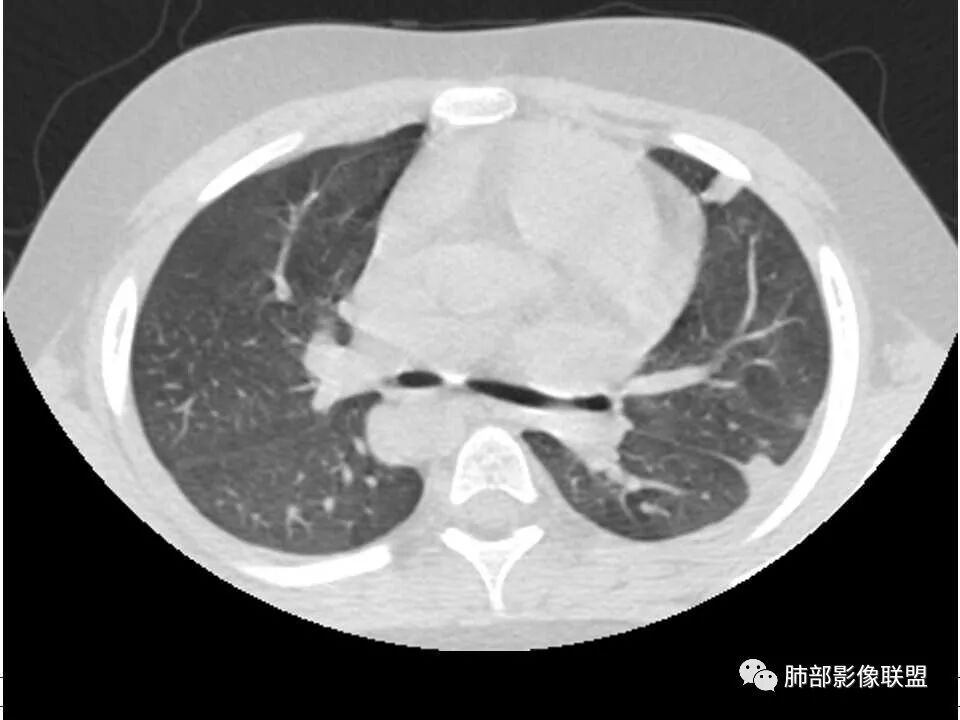

患者儿童,因右下肢疼痛伴肿胀14天就诊。病程中有发热及伴随症状。膝关节MRI提示右侧膝关节及右髌骨髁异常信号影,右膝髌上囊及关节腔内少量积液。胸部CT:双肺胸膜下多发结节影,部分结节空洞形成,且结节周围可见血管集束征。综合考虑血源性脓毒性肺栓塞、坏死性肺炎。右侧骨髓炎、血播性金葡菌肺炎,鉴别其他特殊感染及血管炎。

胸部ct:双肺多发空洞,结节,外带下叶为主,空洞内外光滑,有血管滋养征,综合病史及影像考虑脓毒性肺栓塞,结合病史,金葡可能性大。

小儿,急性起病,下肢疼痛,mr提示骨髓水肿,临床化验炎性指标高,考虑金葡菌骨髓炎,双肺多发结节,以血管支气管束及胸膜下分布为主,部分结节近端与血管相连,部分结节可见空腔,内壁光整,部分囊腔有张力,考虑骨髓炎并肺内血播感染,金葡?

2.双肺多发片影,随机分布,多空洞或囊腔,胸膜下多楔形影,气道未见受累等等符合脓毒血症影像学表现,尤其是金葡。

1. 多发胸膜下外周结节、< 3 cm 的楔形影和滋养血管征 CT 表现;

4.经恰当的抗生素治疗,肺部浸润影吸收。滋养血管征为一支血管影连接肺部周边病灶,在 2/3 以上患者出现,可作为高度提示 SPE 的征象。